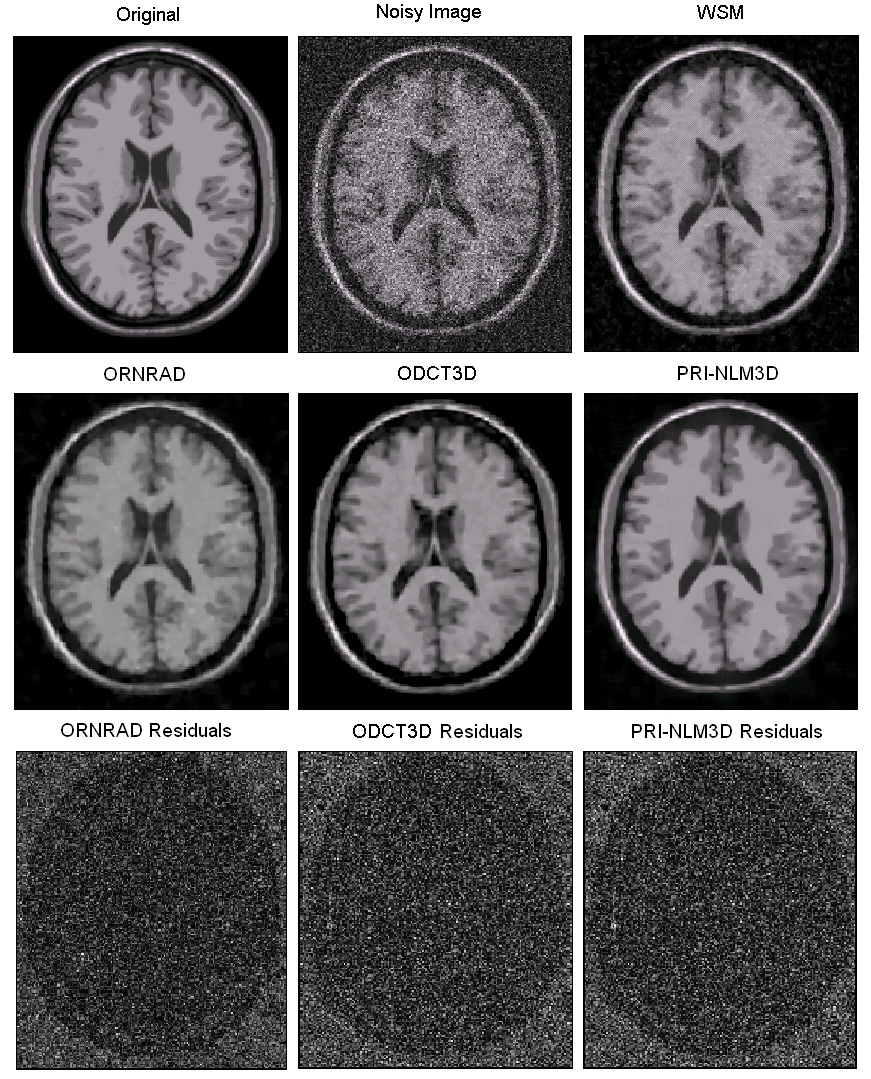

Example results for 15% of Rician noise.